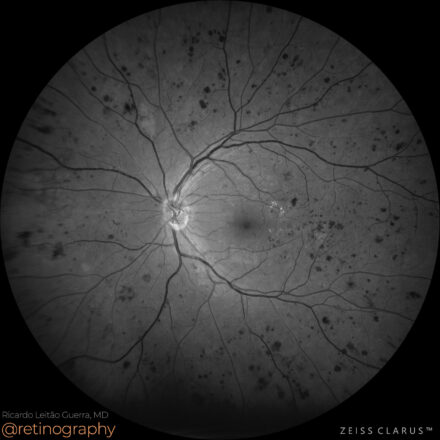

Asymptomatic BRVO

68yo

68yo A superior nasal branch retinal vein occlusion (BRVO) is usually asymptomatic, as the macula is typically spared. These cases are often identified incidentally during routine examination. Fluorescein angiography (FA) reveals localized capillary nonperfusion in the affected quadrant, indicating retinal ischemia. Despite the absence of symptoms, close follow-up is essential to […]